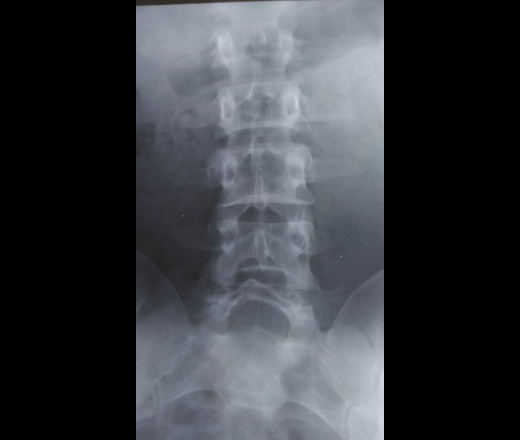

Пол пациента: Мужской пол Тип патологии: Травма Область исследования: Скелетно-мышечная система Методы исследования: Rg Нет ли перелома на представленных снимках Спасибо ID:76114 Цель публикации: Консультация Вс, 01/04/2018 - 16:06 #1 В.И. Не на сайте Был на сайте: 4 месяцев 5 дней назад Зарегистрирован: 22.09.2015 - 17:55 Публикации: 2321 Качество не позволяет сделать однозначный вывод, но думаю нет перелома. Вс, 01/04/2018 - 17:04 #2 И.Бондаренко Не на сайте Был на сайте: 5 часов 46 минут назад Зарегистрирован: 13.09.2011 - 22:55 Публикации: 9208 В.И. wrote: Качество не позволяет сделать однозначный вывод +1. Обычно делаю томограммы чтобы найти перелом.

Качество не позволяет сделать однозначный вывод, но думаю нет перелома.

+1. Обычно делаю томограммы чтобы найти перелом.